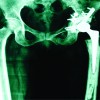

A 48-year-old woman presented with numbness and pain of her right lower extremity 2 days before her first visit. She visited our hospital because of worsening of pain. She was treated for asthma. On physical examination, we noted muscle weakness in the right lower extremity. On the manual muscle test (MMT), the tibialis anterior (TA) and extensor hallucis longus (EHL) were 3/5, and gastrocnemius and flexor hallucis longus (FHL) were 4/5. She denied low back pain. Straight leg raising (SLR) was positive at 70 degrees; however, the femoral nerve stretch test was negative. Deep tendon reflexes were normal. An X-ray revealed degenerative scoliosis at L5–S1 (Fig. 1). Magnetic resonance imaging (MRI) revealed a disc herniation at L5–S1, but there was no significant nerve root compression or cord compression (Fig. 2). Nerve conduction velocity testing in the peroneal nerve revealed that the motor nerve conduction velocity was 51.5 m/s (Fig. 3). When the ankle brachial index was measured to evaluate vascular lesions, a decrease of 0.78 on the right and 0.73 on the left was observed (reference value: 0.91–1.40). Considering the possibility of peripheral arterial disease of the lower extremities, we performed arteriography of the lower extremities but found no significant vascular lesions. Based on these results, the initial diagnosis was LDH and we initiated symptomatic treatment using only an extract from inflamed rabbit skin inoculated with vaccinia virus (Neurotropin®).